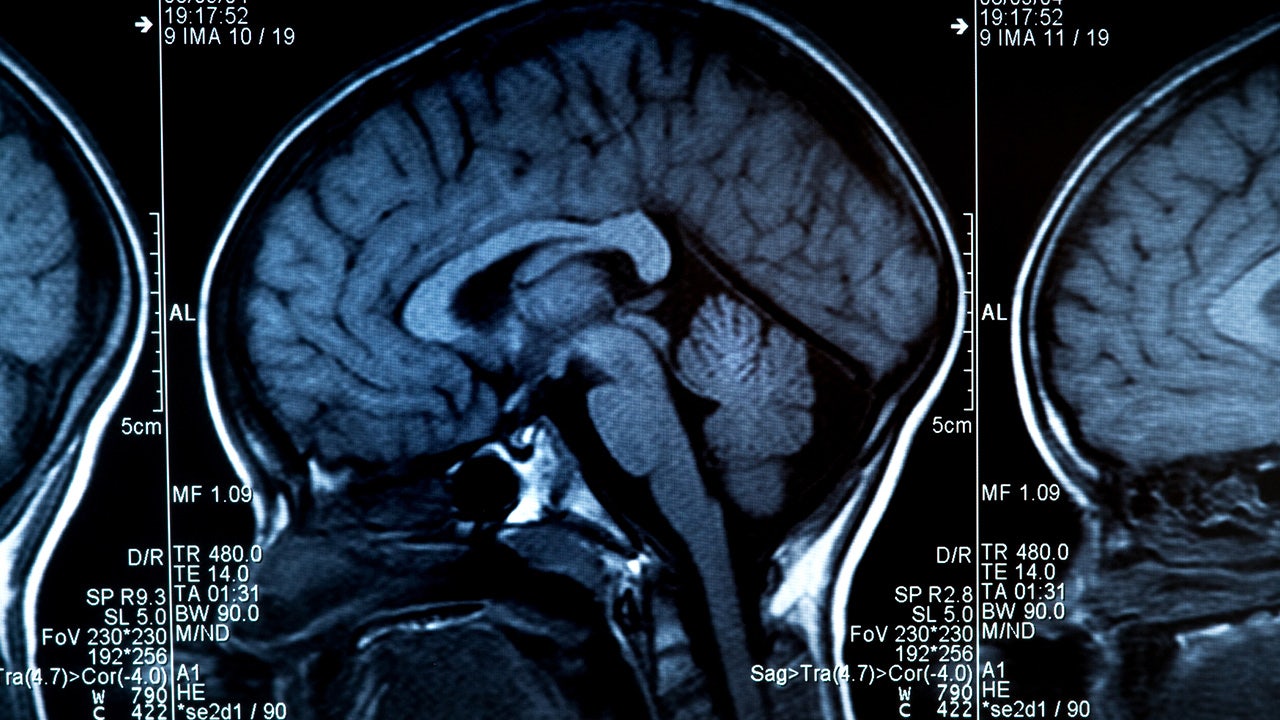

FILE - MRI scan of human brain and skull. (Getty Images)